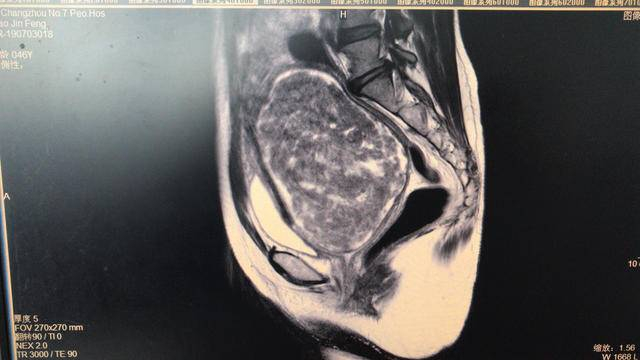

扬子晚报网9月23日讯 (通讯员 瞿云 记者 张斌)“医生、医生”,前些天,夜间一阵急促呼叫,常州市民赵女士被家人由轮椅夜间急诊推到了常州七院妇科病房,原来她小便不能自解,腹痛难忍来院就诊,接诊的妇产科副主任医师孙光宇立即给赵女士进行了详细的检查,检查结果让大家吓了一大跳,赵女士有一巨大的宫颈肌瘤,直径已达15cm,此次发病主要是因为这个宫颈肌瘤太大了,占据了整个盆腔压迫膀胱导致赵女士不能小便,遂立即将赵女士收住院进行了手术治疗,术后赵女士拔除导尿管,目前已经可以自行解小便了。

术后医生在与赵女士的交谈中得知,赵女士已有10年未进行妇科检查。据孙光宇介绍,子宫肌瘤是妇科最常见的良性肿瘤,常见于30-50岁的妇女,20%育龄妇女有子宫肌瘤,因肌瘤多无或很少有症状,但通过定期检查均可发现。子宫肌瘤根据发生部位不同,分子宫体肌瘤、子宫颈肌瘤;而宫颈肌瘤发生率很低,往往很多人忽视,它主要可引起排尿困难、尿潴留等症状,部分因肌瘤巨大,嵌入盆腔内,压迫输尿管,可形成输尿管扩张、肾盂积水甚至一侧肾无功能。孙光宇再次提醒广大育龄妇女,一定要重视自己的健康,定期进行妇科体检,最好每半年做一次妇科B超及妇科检查。一旦查出有子宫肌瘤也不要惊慌,对于瘤体直径小于5cm,无症状,未引起月经改变者,一般不需治疗,特别是近绝经期妇女,定期随访即可。但对于肌瘤生长过快,引起月经改变或特殊部位的肌瘤,如粘膜下肌瘤、宫颈肌瘤、阔韧带肌瘤等需积极治疗,首选手术治疗,避免发生恶性病变。呼吁女性定期体检,多关注自身保健,一旦发现身体异常情况,及时就医,配合医生进行专业治疗。